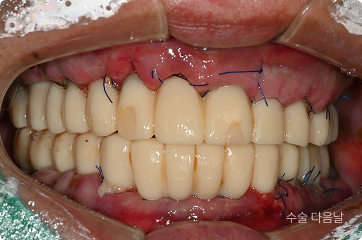

치료 후

• 대부분의 치아 상실, 식사 및 생활 불가능

• 하루만에 전체 임플란트 식립

3일만에 전체 즉시 기능 예비치아 장착

• 6개월 후 최종 보철까지 완성